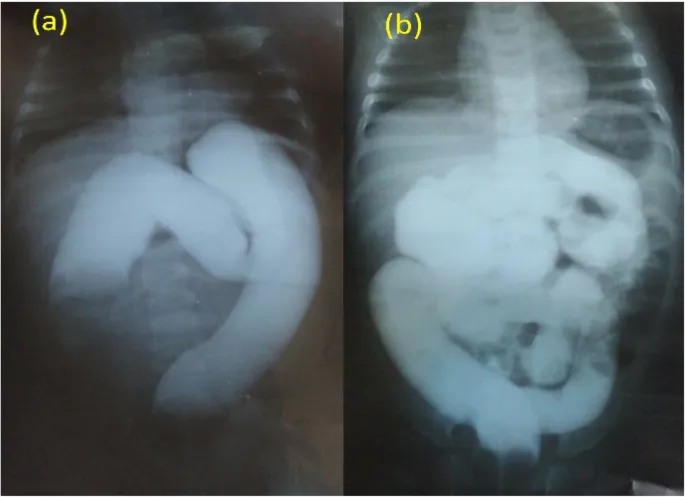

- Contrast Enema (Air/Barium/Water-soluble):

- Diagnostic & therapeutic.

- Shows 'crescent sign'/'meniscus sign'.

- ⚠️ Contraindicated: peritonitis, perforation.